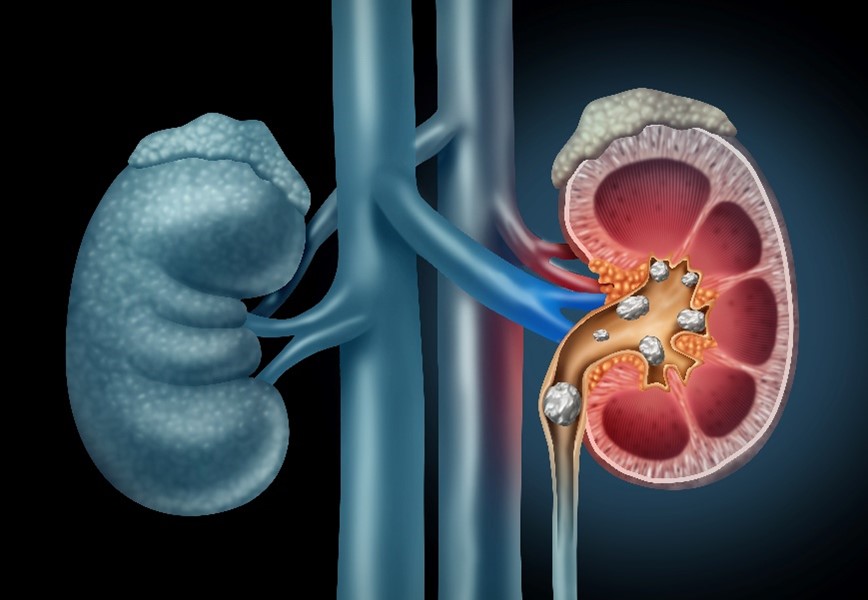

Myeloma cast nephropathy, also known as light chain cast nephropathy, is a severe kidney complication of multiple myeloma, a type of cancer that affects plasma cells. It occurs when large amounts of abnormal proteins, called light chains, are produced and build up in the kidneys, causing significant damage. Our specialists provide compassionate and timely care to diagnose and manage this complex condition.

Excess light chains can form dense blockages, or “casts,” that obstruct the kidney’s filtering tubules and may cause kidney failure. This type of damage is a primary cause of myeloma kidney disease. Symptoms may include a sudden decrease in urine output, swelling in the legs, fatigue, or nausea, although signs may not be noticeable in the early stages.